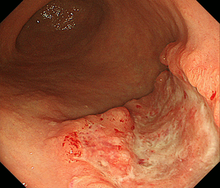

胃がんは、胃の壁の最も内側にある粘膜内の細胞が、何らかの原因でがん細胞になって無秩序に増殖を繰り返すことで生じます。胃がん検診などの検査で見つけられる大きさになるまでには、通常何年もかかるといわれています。胃がんの診断には胃の内側から内視鏡(胃カメラ)で観察することにより診断が可能であり、胃がんの部分がイボのように盛り上がったり、潰瘍を形成し陥凹している部分、色調の変化した部分などを詳しく観察します。生検検査でがん細胞を認めると診断が確定します。胃がんの内視鏡写真を提示します(図1)。

がん細胞の増殖の仕方によって「分化型胃がん」と「未分化型胃がん」に分かれます(図2)。分化型胃がんでは、もとの正常な細胞の特徴を残したまま塊を作って大きくなります。一方、未分化型胃がんは、もとの細胞の構造がほとんど見られずバラバラに広がり、がんの範囲も分かりにくいです。とくに未分化型胃がんのなかで、粘膜に発生した癌が表面を広がらないで粘膜の深いところを這うように広がって行くタイプ(スキルス胃がん)では診断がつきにくく、かなり進行しないと見つかりにくい場合もあります。